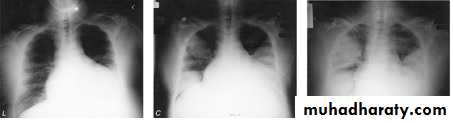

Coexistent debilitating illness and often preceded by influenza. Radiographic features include multilobar shadowing, cavitation, pneumatoceles and abscesses. Dissemination to other organs may cause osteomyelitis, endocarditis or brain abscesses. Mortality up to 30%.

Chest X-ray show multiple lung abscessStaphylococcus pneumonia